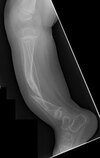

What is this condition? What is the natural hx? What is it associated with?

congenital posteromedial bowing of the tibia. The natural history of this condition is gradual improvement, with the patient being left with a limb-length discrepancy at skeletal maturity. Bowing is associated with a calcaneovalgus deformity of the ipsilateral foot. There is no association with scoliosis and skin lesions. There is no increased risk for bone tumors or neurologic issues with congenital posteromedial bowing of the tibia